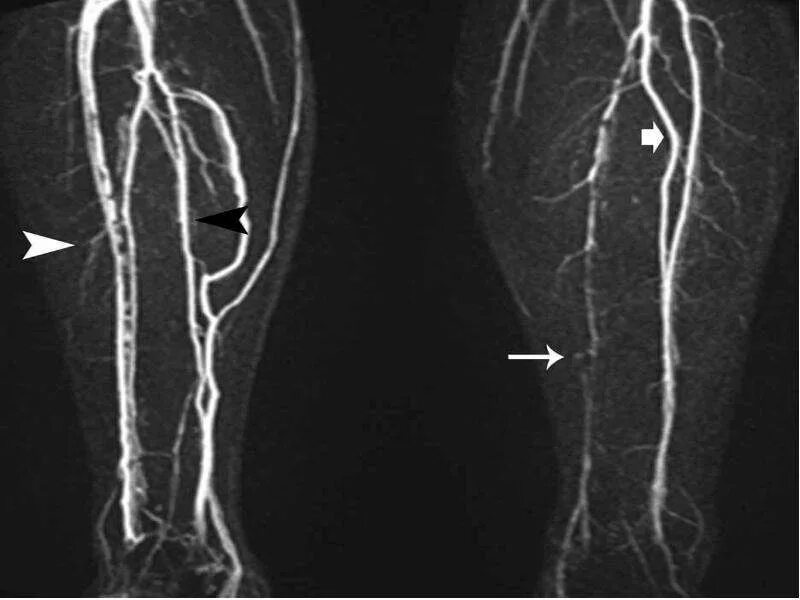

Облитирующий атеросклероз